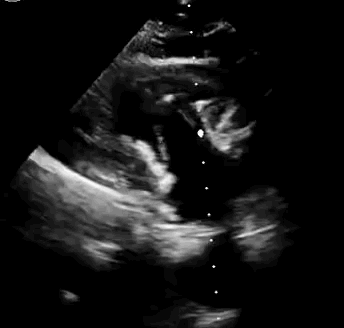

本次臨床前研究經右側頸靜脈置入LuX-Valve Plus輸送系統(tǒng)可調彎鞘管,在DSA及超聲引導下將人工三尖瓣瓣膜植入到原有三尖瓣位置,利用獨特的錨定技術將人工瓣膜支架可靠固定在預定的位置。

上海中山醫(yī)院葛均波院士、錢菊英院長、周達新教授、潘文志教授、潘翠珍教授、李偉教授共同完成此次臨床前研究。術后葛均波院士對Lux-Valve Plus的器械操作性能給予了高度評價,DSA和超聲影像也顯示出在本次研究中Lux-Valve Plus的安全性和有效性俱佳。